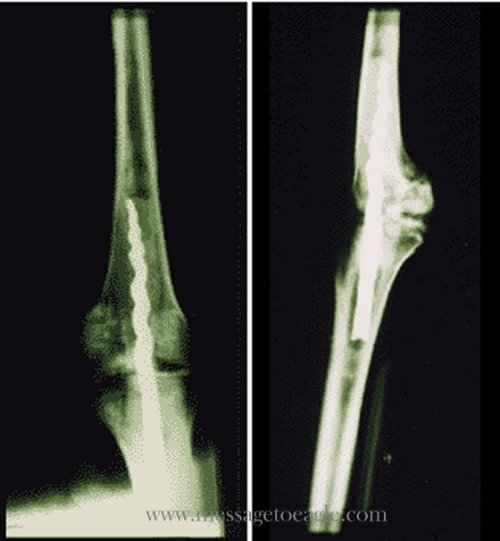

Hình ảnh X-quang cho thấy chiếc ốc vít dài trong chân của xác ướp. (Ảnh: messagetoeagle.com)

Một ốc vít kim loại 9 inch được tìm thấy trong xác ướp 2.600 năm tuổi trong chân của một vị linh mục Ai Cập tên là Usermontu đã gây chấn động trong giới khoa học toàn thế giới.

Năm 1996. Giáo sư Wilfred Griggs, nhà Ai Cập học tại Đại học Brigham Young đang thực hiện nghiên cứu về DNA xác ướp trong 6 xác ướp nằm tại Bảo tàng San Jose Rosicrucian, bỗng phát hiện thấy tia X hiển lộ ra một ốc vít kim loại ở gần xương bánh chè của Usermontu.

Xác ướp cho thấy bằng chứng của một ca phẫu thuật tiên tiến đã được thực hiện cách đây 2.600 năm. Nhóm nghiên cứu vô cùng kinh ngạc khi thấy chiếc đinh ghim đã được tạo ra với nguyên tắc cơ sinh học hiện đại ngày nay nhằm cố định xương.